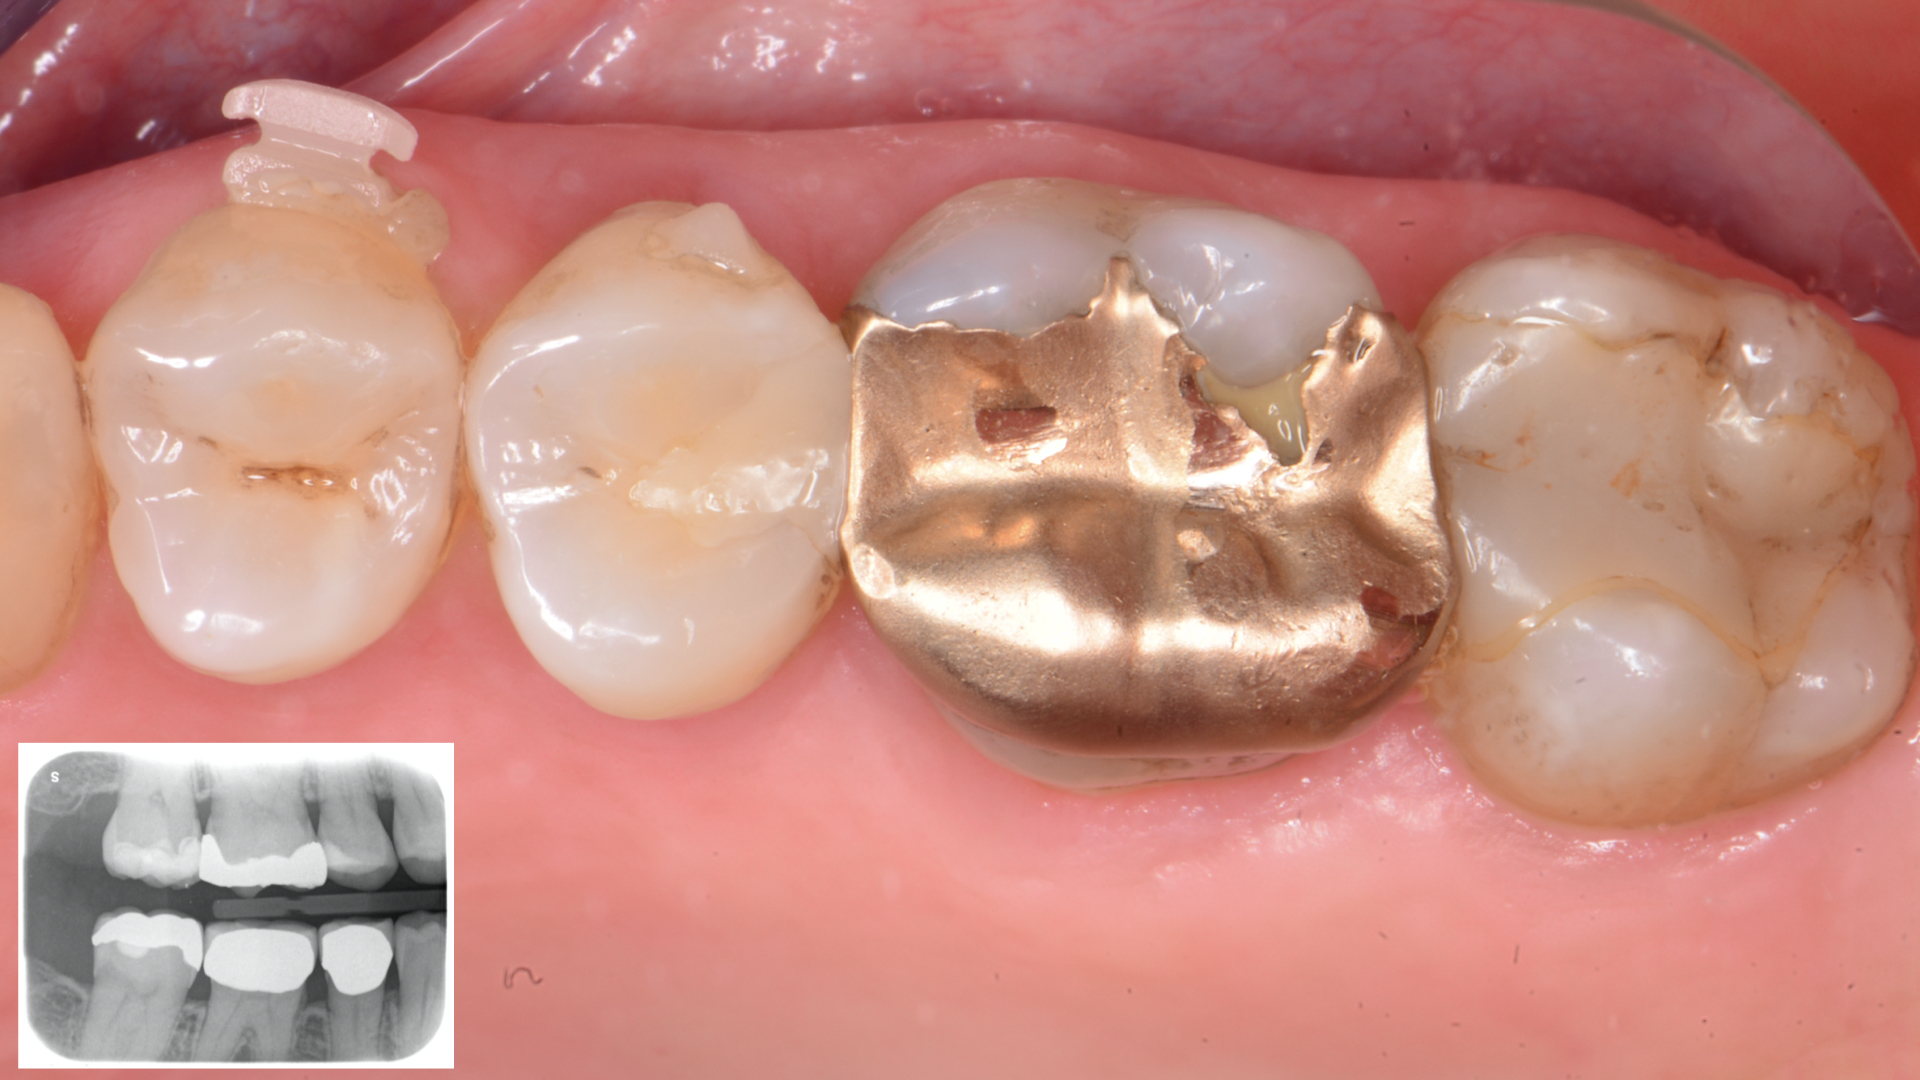

Figure 11

Figure 11.  Final after finishing and polishing proceduresFigure 12. One month Control. Occlusal view (Rx above)